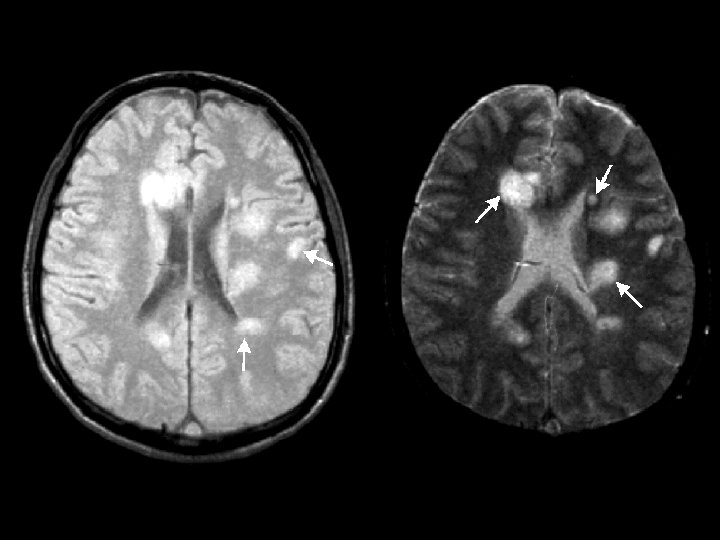

MULTIPLE SCLEROSIS (MS) * Chronic unpredictable disease of CNS with four possible clinical courses * Characterized by patches of demyelination and inflammation of myelin sheath * Prevalence higher in Northern Hemisphere • North of 37 th parallel (125 cases /100, 000) • South of 37 th parallel (70 cases /100, 000) * Female to male ratio of 2: 1

MULTIPLE SCLEROSIS (MS) * Effector mechanisms • Myelin basic protein is primary autoantigen for CD 4 TH 1 cells * Radiology diagnosis • MRI for detecting demyelinating lesions (plaques) • Laboratory diagnosis • High resolution protein electrophoresis for • Oligoclonal bands in CSF